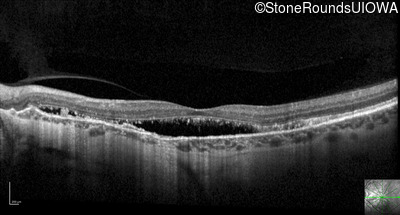

Optical Coherence Tomography - Right - 20/20 -3 sc

Exemplar / OCT Stack